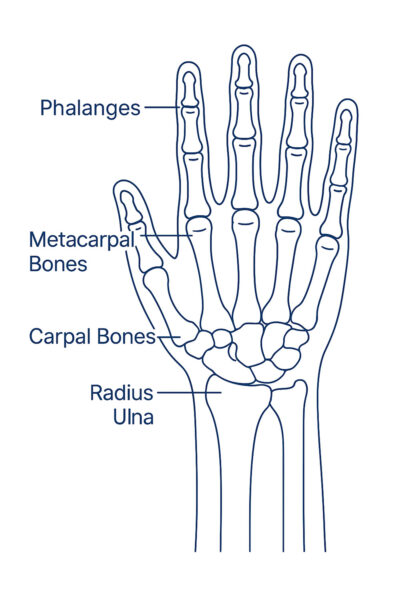

Bones in the wrist include:

- Phalanges

- Metacarpal Bones

- Carpal Bones

- Radius

- Ulna